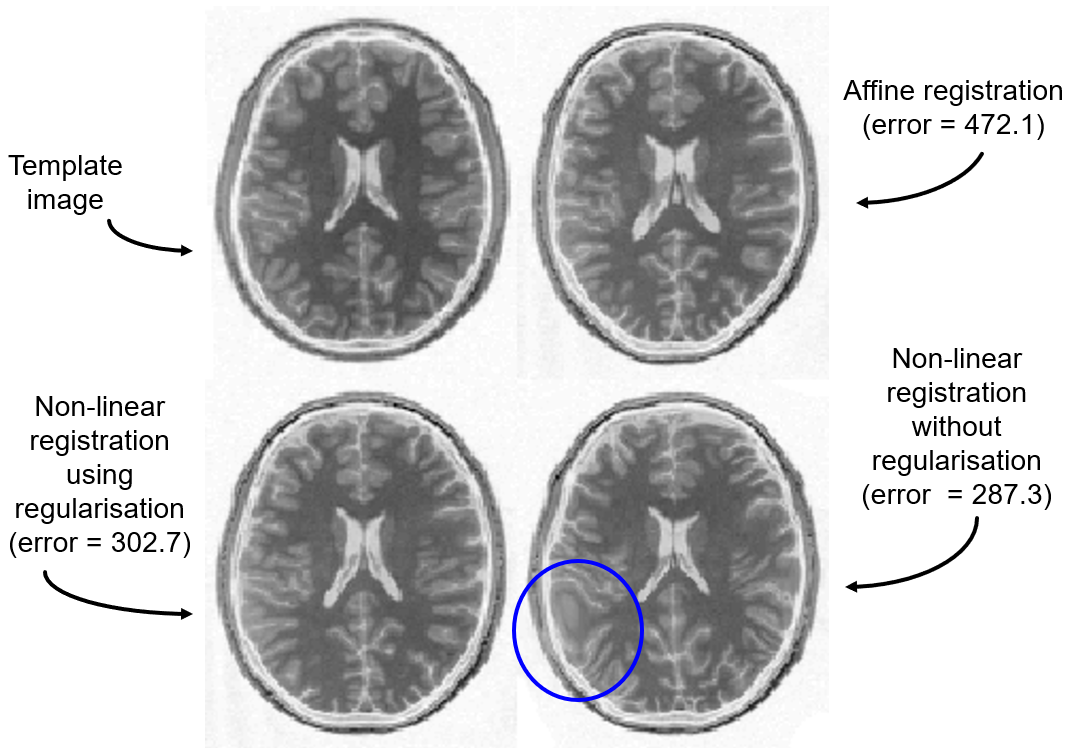

线性配准就是在做仿射变换,通过乘以一个由贝叶斯后验估计出的变换矩阵来实现,是线性操作。仿射变换包括旋转,平移,缩放和错切1等,前两者是刚体变换。仿射变换是对图像整体进行操作,所以只能匹配整体的位置和大小,所以配准后的脑袋在形状和组织位置上还有较大差异,如图3左图,图源4

在这里插入图片描述

非线性配准是在对线性配准后的图像进行扭曲和变形(warping , deforming)操作,将被试图像的脑沟和其他结构尽量对到模板上,使其与模板尽可能的像。操作过程由最优化理论和一些平滑度量控制,目标是最小化平方误差函数1。非线性配准后不同被试的脑袋形状和组织形状和解剖位置已经变得非常相似——相同空间坐标对应的解剖位置基本一致,如图4右图,图源4

线性配准与非线性配准

图4.线性配准与非线性配准

另外还有种原因可能导致配准结果坏掉,那就是非线性配准优化过程中过拟合——太追求误差小了,而把某些组织结构给抹掉的,如图5蓝色圈出部分,图源5。可以通过加正则项或者惩罚项来减少过拟合,熟悉最优化理论或者机器学习的朋友应该会对这个概念比较熟悉。不过一般的工具包,如SPM,FSL,CAT12等都考虑了这个的,只需点点点就可以了。

非线性配准与过拟合

图5.非线性配准与过拟合